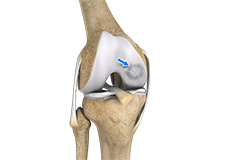

Articular Cartilage and Menisci of the Knee

Movement of the bones causes friction between the articulating surfaces. To reduce this friction, all articulating surfaces involved in the movement are covered with a white, shiny, slippery layer called articular cartilage. The articulating surface of the femoral condyles, tibial plateaus and the back of the patella are covered with this cartilage. The cartilage provides a smooth surface that facilitates easy movement.

To further reduce friction between the articulating surfaces of the bones, the knee joint is lined by a synovial membrane that produces a thick clear fluid called synovial fluid. This fluid lubricates and nourishes the cartilage and bones inside the joint capsule.

Within the knee joint, between the femur and tibia, are two C-shaped cartilaginous structures called menisci. Menisci function to provide stability to the knee by spreading the weight of the upper body across the whole surface of the tibial plateau. The menisci help in load-bearing i.e. it prevents the weight from concentrating onto a small area, which could damage the articular cartilage. The menisci also act as a cushion between the femur and tibia by absorbing the shock produced by activities such as walking, running and jumping.

Ligaments of the Knee

Ligaments are tough bands of tissue that connect one bone to another bone. The ligaments of the knee stabilize the knee joint. There are two important groups of ligaments that hold the bones of the knee joint together, collateral and cruciate ligaments.

Collateral ligaments are present on either side of the knee. They prevent the knee from moving too far during side to side motion. The collateral ligament on the inside is called the medial collateral ligament (MCL) and the collateral ligament on the outside is called the lateral collateral ligament (LCL).

Cruciate ligaments, present inside the knee joint, control the back-and-forth motion of the knee. The cruciate ligament in the front of the knee is called anterior cruciate ligament (ACL) and the cruciate ligament in the back of the knee is called posterior cruciate ligament (PCL).